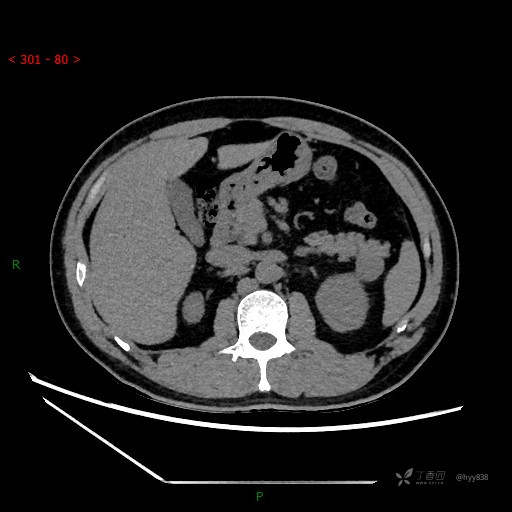

胰腺CT平扫

增强动脉期

增强静脉期

CT值

42hu 48hu 57hu